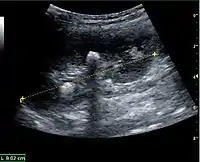

Complex cysts can have membranes dividing the fluid-filled center with internal echoes, calcifications or irregular thickened walls. The complex cyst can be further evaluated with Doppler US, and for Bosniak classification and follow-up of complex cysts, either contrast-enhanced ultrasound (CEUS) or contrast CT is used (Figure 6). The Bosniak classification is divided into four groups going from I, corresponding to a simple cyst, to IV, corresponding to a cyst with solid parts and an 85–100% risk of malignancy.[1] In polycystic kidney disease, multiple cysts of varying size in close contact with each other are seen filling virtually the entire renal region. In advanced stages of this disease, the kidneys are enlarged with a lack of corticomedullary differentiation (Figure 7).[1]

Figure 6. Complex cyst with thickened walls and membranes in the lower pole of an adult kidney. Measurements of kidney length and the complex cyst on the US image are illustrated by '+' and dashed lines.[1]